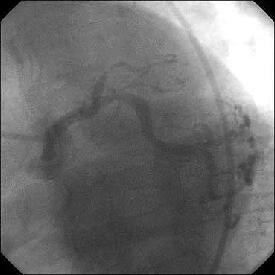

�Ǘ��72�Ώ����Brisk factor��HT, HL, DM�ł��B

��2�T�ԑO�̔��ǂƎv����Recent MI�ł��BLAD#7: total��Tristar3.0�~18?�����

�܂����B

����LCx ostium: 75%�ł��B������PCI���悤�Ǝv���̂ł����A�ǂ̂悤��strategy

���l������ł��傤���H

���Ȃ݂ɓ��@�ł�DCA�g�p�o���҂͂��܂���B

DCA�ł���l��A��Ă���A�Ƃ����I�������܂߂Č䏕��������K���ł��B

�X�������肢���܂��B

|

|

|

|

|

����������������������������������������������������������������������������